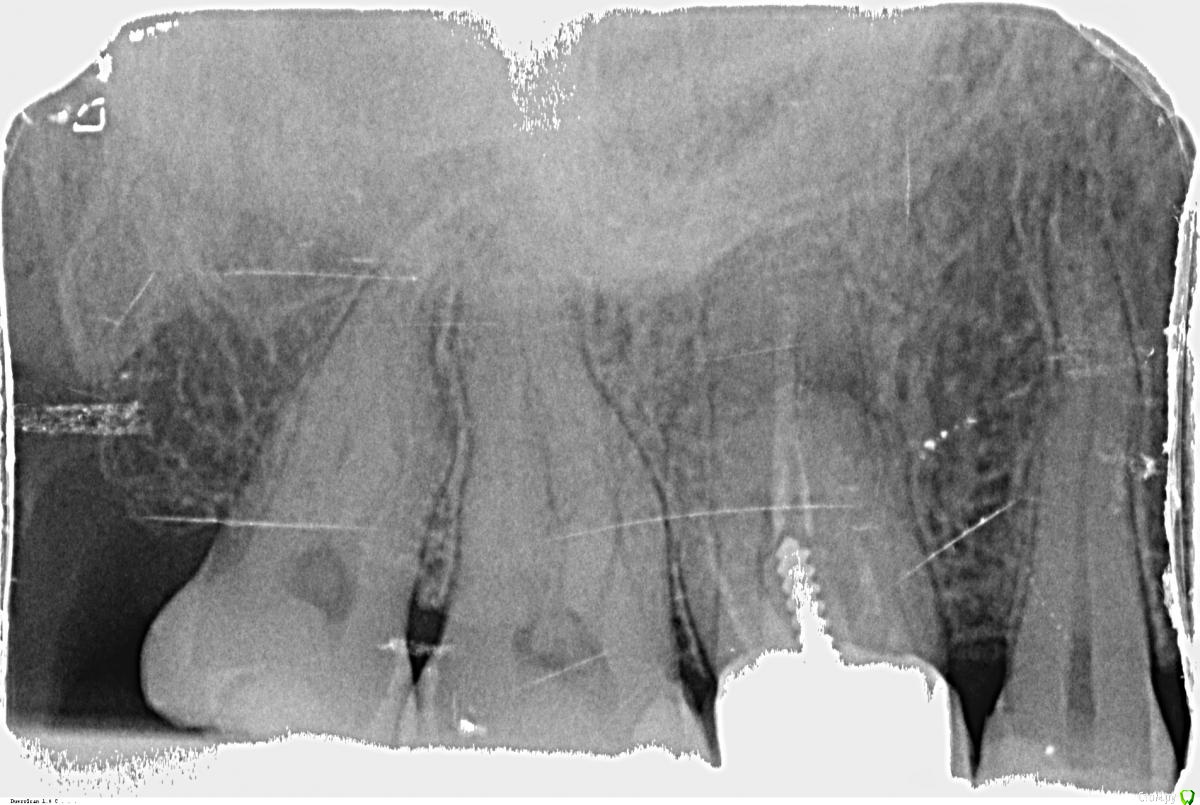

krokomot Опубликовано 26 октября, 2015 Поделиться Опубликовано 26 октября, 2015 похоже на перфорацию корня, надо смотреть очно Ссылка на комментарий

DmitrySH Опубликовано 26 октября, 2015 Поделиться Опубликовано 26 октября, 2015 К эндодонтисту.Снять коронку, достать штифт, оценить состояние дна полости зуба, если все ок, то ревизия каналов. Дождаться закрытия "свища" и все в обратном порядке.А вот если выявятся проблемы с разрушением самого зуба ( что можно предположить по локализации очага воспаления) тогда уже по ситуации. 3 Ссылка на комментарий

x3m Опубликовано 7 ноября, 2015 Поделиться Опубликовано 7 ноября, 2015 ищите третьего стоматолога Полгода в каналах лечить нечего.Как Вам и отвечали, надо снять коронку, весь композит, извлечь штифт и оценить объем оставшихся тканей зуба, целостность дна (область зуба между каналами), отсутствие перфорации/трещины. Итого, вскрытие покажет:1. Зуб лечибелен (есть запас тканей, дно зуба целое, перфорации и трещины нет) - нашли все 4 канала, их перепломбировали, установили ВКВ и коронку. За недели 2 (+ / -) управитесь.2. Зуб нелечибелен (кариес глубоко под десной, трещина/перфорация, разрушено дно, невозможно перелечить каналы)- удалили и через 1-1,5 мес (если не сразу) установили имплантат. П.С. Что там чистить будут, кода "выдерут" - неважно, главное - чтоб чисто 3 Ссылка на комментарий

СветланаАндревна Опубликовано 8 ноября, 2015 Автор Поделиться Опубликовано 8 ноября, 2015 Спасибо за ответы. Честно говоря, я уже на удаление настроилась. Теперь опять в поиске стоматолога.Забыла добавить. На томографии ортопед увидел гранулему зуба и кисту(откуда этот свищ и идет). Но я так понимаю, на "план по вскрытию" от x3m это никак не влияет. Ссылка на комментарий

СветланаАндревна Опубликовано 18 ноября, 2015 Автор Поделиться Опубликовано 18 ноября, 2015 Успели что то сделать? Да. Удалила таки вчера... Теперь меня на 1 зуб меньше.Нашла таки двух еще врачей ( один из них с форума по томографии проконсультировал), они готовы были порассматривать зуб под микроскопом, но киста между корнями, которую видно на томограмме, и это все 4 врача + вчерашний хирург, говорят, скоре всего перфорация. Не стала я тратить деньги и время на этот зуб, ибо по томограмме воспалены еще 2 зуба с другой стороны. Буду их лечить. А в место этого имплант через полгода. Думаю, можно закрыть тему. Всем откликнувшимся, большое спасибо. Ссылка на комментарий